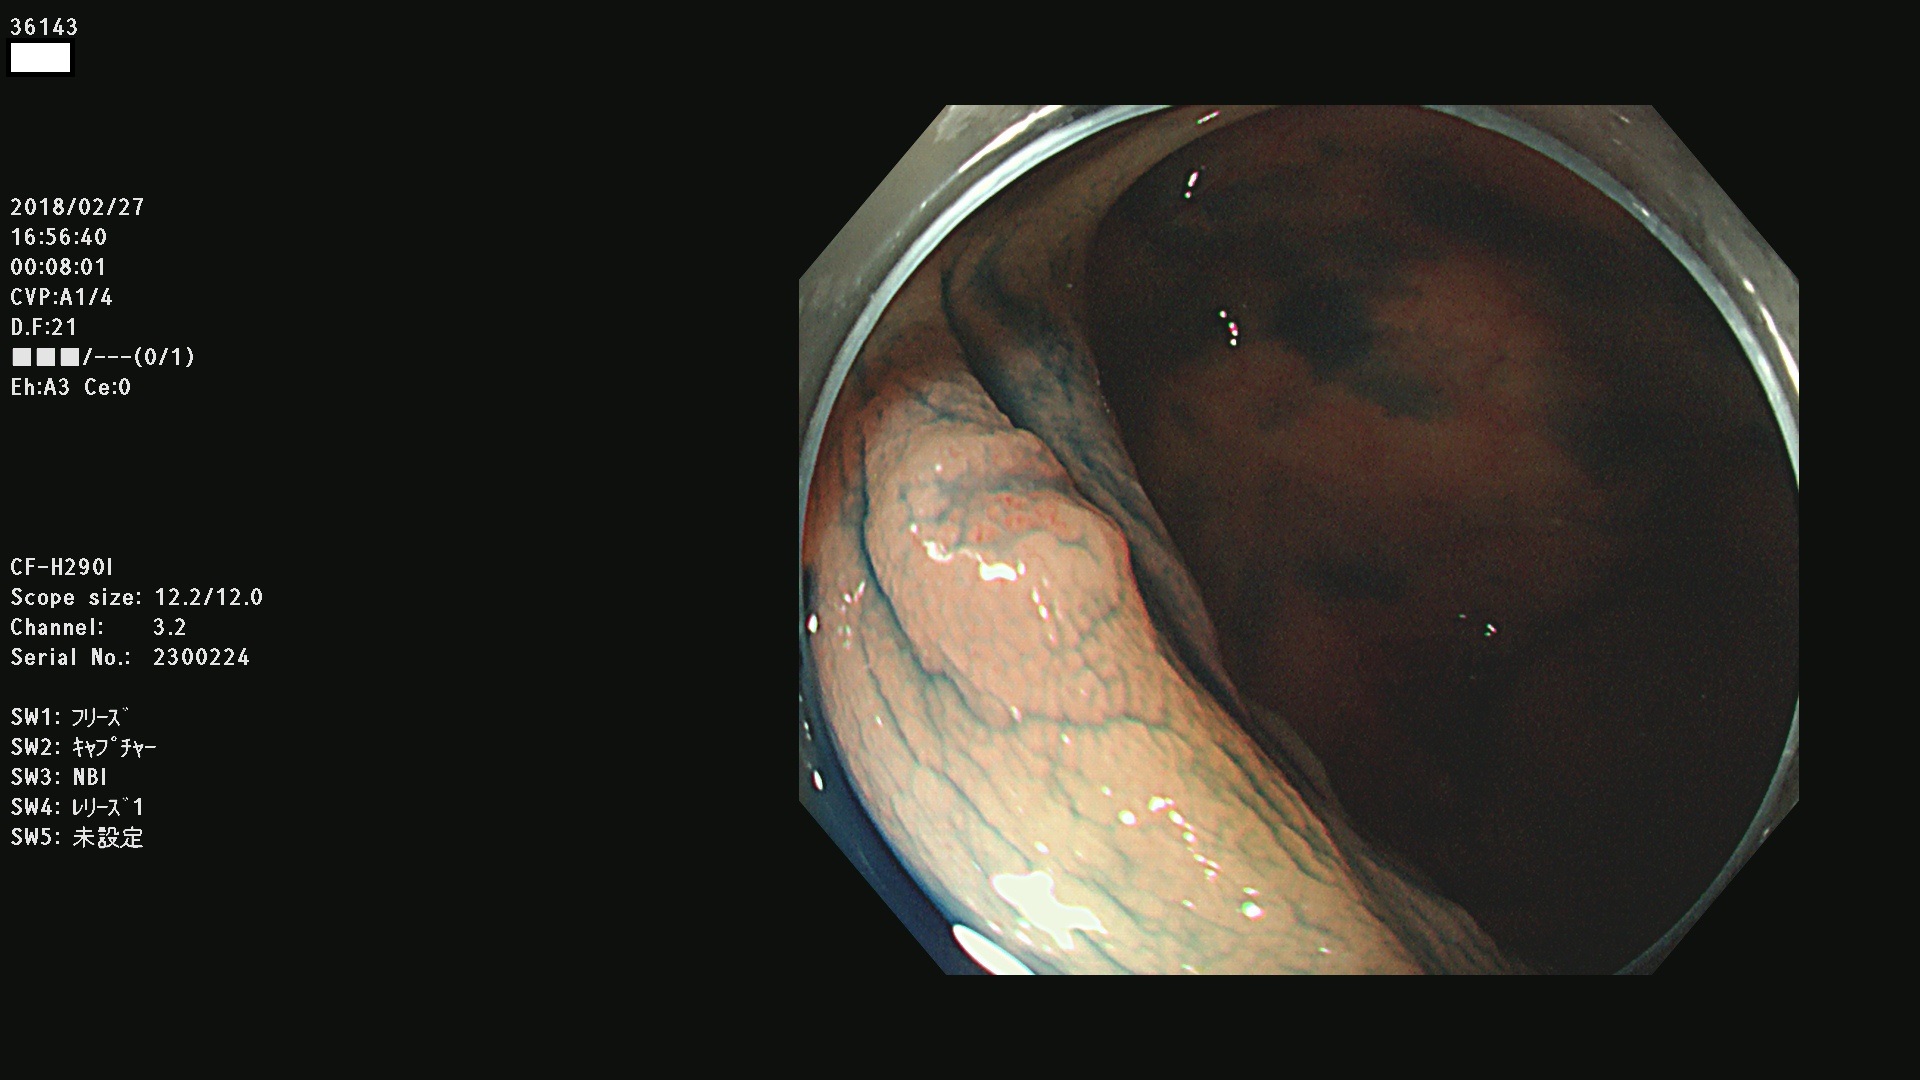

発見困難で危険性の高い平坦型病変(上記100名より抽出) ![]()